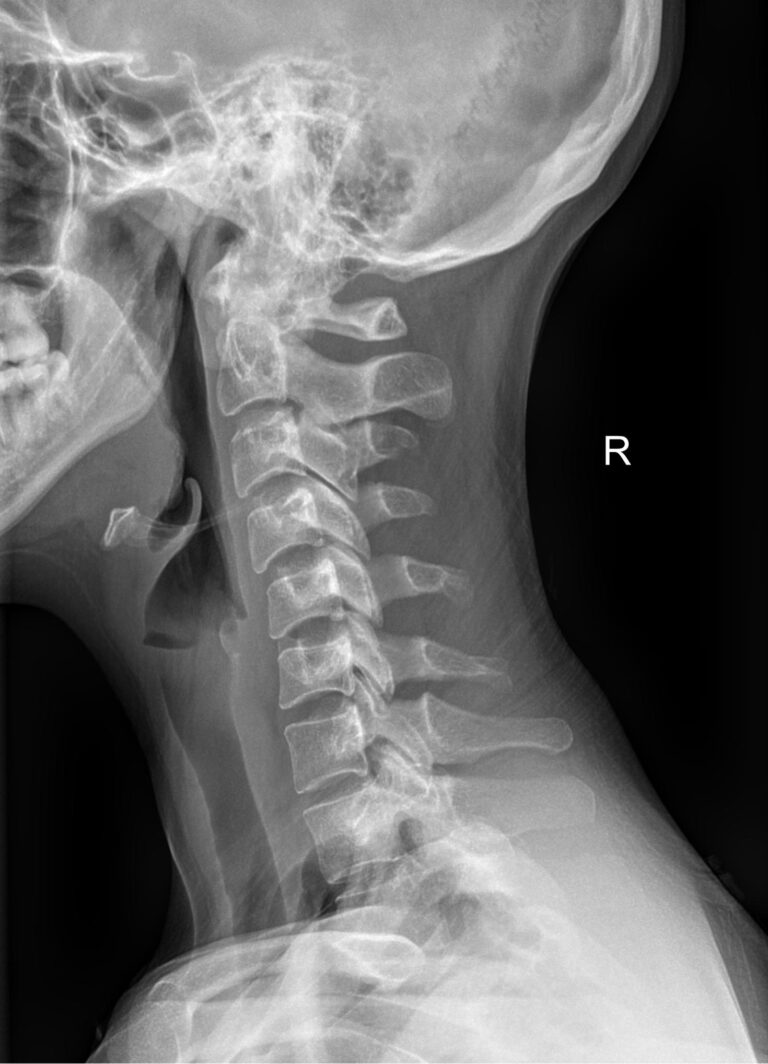

Функциональные исследования помогают выявить гипермобильность шейных позвонков или функциональный блок. Часто пробы позволяют определить начало остеохондроза, признаки которого на снимках в прямой и боковой проекции еще не заметны.

• Сохранение или сглаживание естественного лордоза в нейтральном положении, то есть на первом снимке;

• Смещение вперед или назад каждого позвонка по отношению к нижележащим при сгибании и разгибании;

• Деформацию передней стенки позвоночного канала из-за смещения позвонков;

• Сужения, расширения или отсутствие изменений межпозвоночных пространств;

• Изменения формы тел позвонков, наличие остеофитов;

• Аномалии развития.

В качестве подготовки необходимо снять все металлические украшения с шеи и головы, расстегнуть пуговицы и надеть защитную накидку. Диагностика выполняется в положении стоя или сидя, всего делается 3 снимка:

• В боковой проекции ― строго боком к детекторной пластине;

• В условиях максимального разгибания головы назад;

• В положении максимального наклона головы вперед.